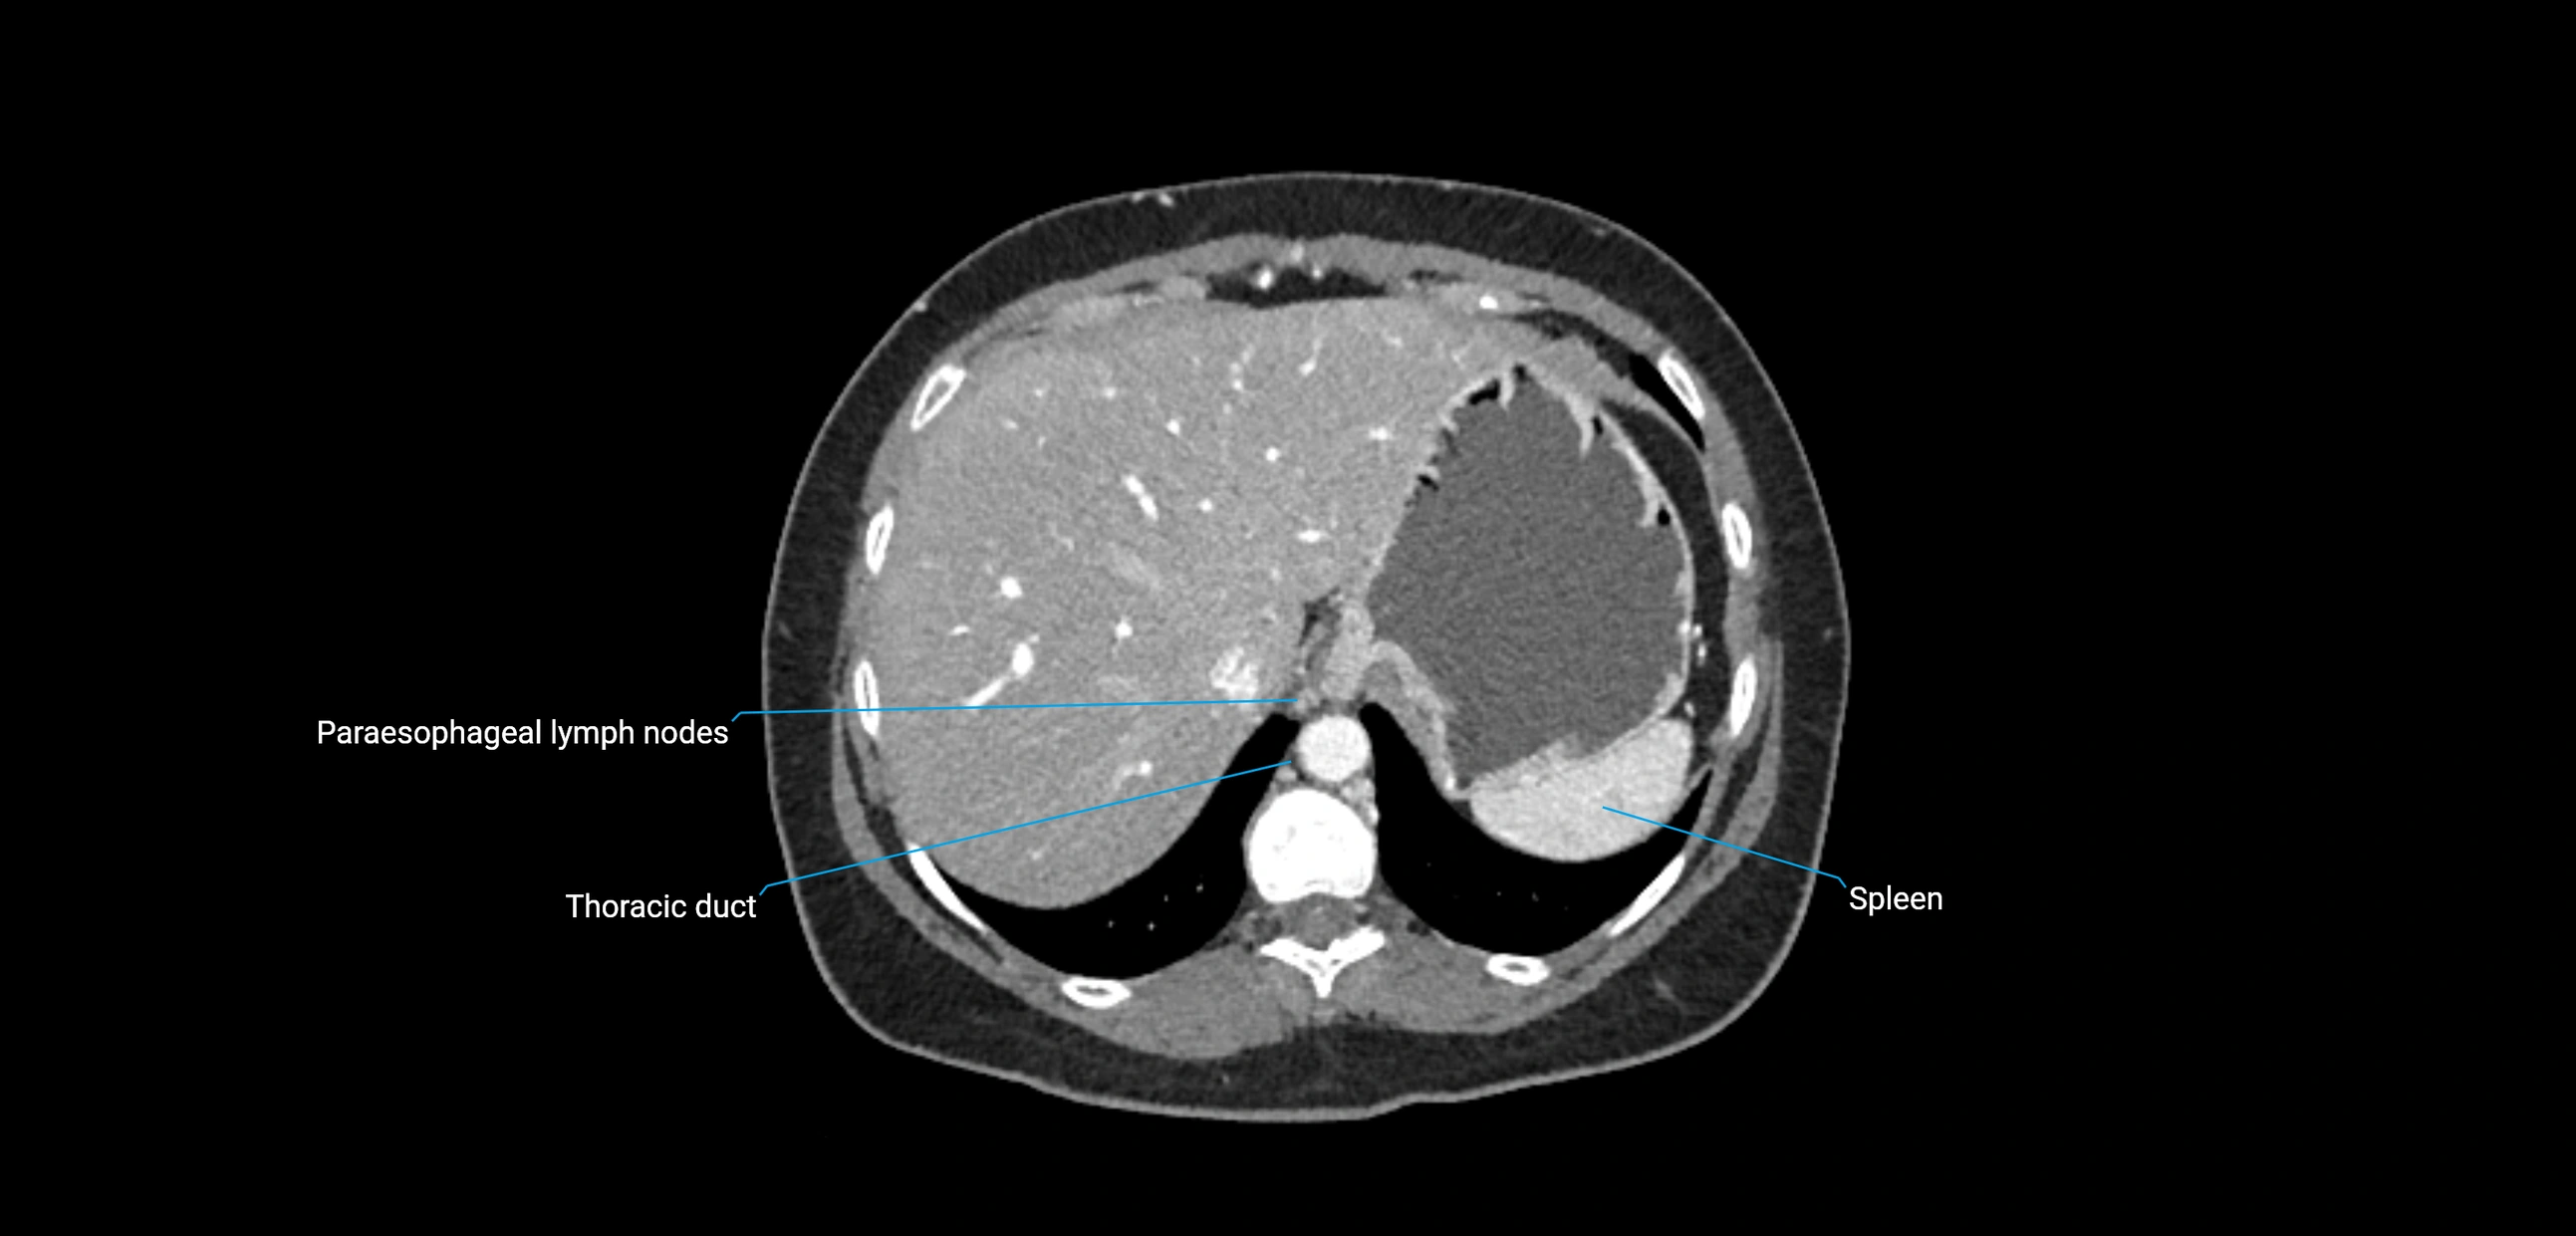

CT image

image